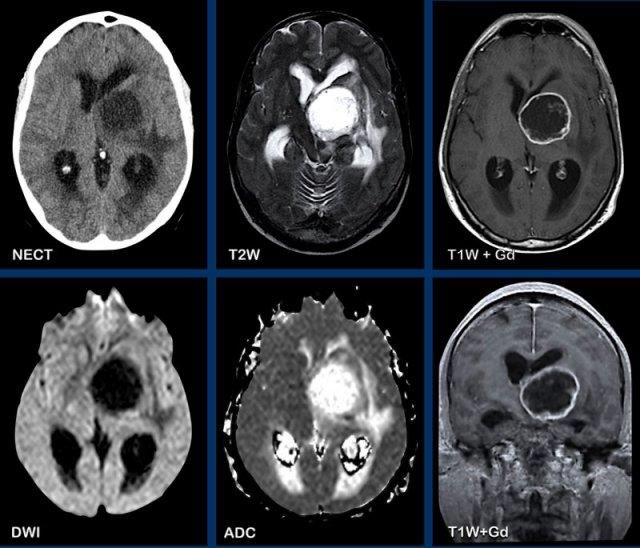

Các hình ảnh này của một phụ nữ 76 tuổi, có biểu hiện lú lẫn sau khi ngã.

Hãy quan sát các hình ảnh trước rồi mới tiếp tục đọc.

Câu hỏi:

- Chẩn đoán có khả năng nhất là gì?

- Những dấu hiệu nào điển hình cho chẩn đoán này?

Các dấu hiệu bao gồm:

- Tổn thương tăng tỷ trọng trên CT không tiêm thuốc cản quang kèm phù não do mạch máu.

- MRI cho thấy nhiều tổn thương ngấm thuốc dạng đặc và hạn chế khuếch tán.

- Trên chuỗi xung T2W, các tổn thương biểu hiện giảm tín hiệu.

- Một tổn thương nằm ở thể chai và một tổn thương khác nằm cạnh não thất.

Tất cả các dấu hiệu này đều điển hình cho u lympho nguyên phát hệ thần kinh trung ương, khác với u lympho hệ thống.

Các khối u này chiếm 6-7% tổng số u hệ thần kinh trung ương và mô học là u lympho tế bào B không Hodgkin.

Chúng thường nằm ở vùng cạnh não thất dưới màng nội tủy, thể chai và hạch nền.

Luôn nghĩ đến u lympho khi gặp tổn thương ngấm thuốc dạng đặc nằm gần não thất.

Hình ảnh tăng tỷ trọng trên CT, giảm tín hiệu nhẹ trên chuỗi xung T2W cũng như hạn chế khuếch tán được giải thích là do mật độ tế bào dày đặc của mô u lympho.

Ở bệnh nhân suy giảm miễn dịch, kiểu ngấm thuốc có thể là dạng vòng nhẫn.

Bệnh nhân này có nhiều phù não, nhưng trong nhiều trường hợp phù não rất hạn chế.